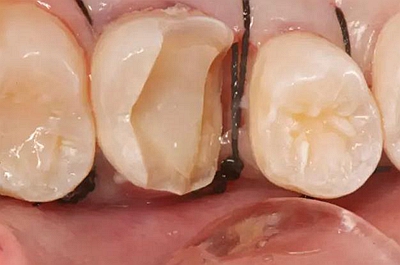

一周后拆除縫線,試戴高嵌體,試戴合適后雙固化粘結(jié)。調(diào)合,拋光。

一周后拆線,口內(nèi)試戴合適,粘結(jié)嵌體。